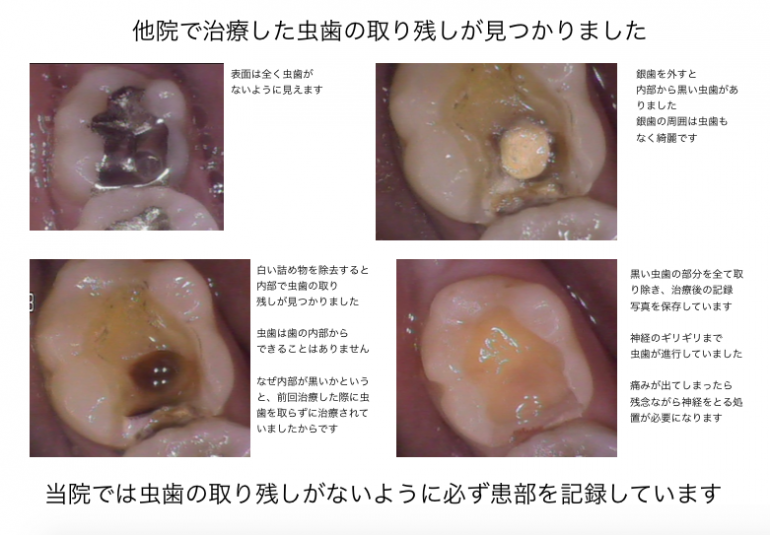

虫歯の治療を受ける場合は、患部の写真を撮って治療してもらえる歯科医院に行くことをオススメしています

当院では治療する場合は、口腔内写真を必ず撮影し、治療前と治療中、治療後で最低3枚以上撮影して、 治療後にどのような状態だったのか写真を撮って説明しています

問題が起きている歯や歯茎を口腔内専用カメラで撮影し治療前と治療後を比較。

治療後にモニターに映して説明しています。

治療途中も虫歯の取り残しがないことを記録で残しているため、治療後に歯に何か気になることがあっても過去の治療内容を見ることができるので安心です。

口腔内写真を取り、患部を拡大することにより、虫歯の取り残しを確実になくししています

A;患部に虫歯の取り残しがないか確認し記録するためです。

治療後は詰め物や銀歯でふさいでしまうためレントゲンで撮影しても小さい虫歯は発見することはできません。

当院は虫歯の取り残しがないようにをしっかり治療し、記録を残しています

歯の内部はどのような治療をしているか患者様はわからないため、治療後は自分の目で虫歯の取り残しがないかどうか確認することをオススメしています

以前治療した銀歯の内部から虫歯の取り残しが見つかった症例

最近治療した歯の内部から虫歯が見つかった症例

歯を直接見て綺麗なのに内部に透過像があると虫歯の取り残しの可能性があります

以前治療したレジン治療の内部から虫歯の取り残しが見つかった症例

銀歯の内部で虫歯の取り残しがあった症例

レジン治療の内部で虫歯の取り残しがあった症例

1本の歯に2回連続で虫歯の取り残しが見つかった症例

上記の写真はここまで虫歯になっていても痛みが全くない症例でした

治療を受ける際は、幹部の写真を撮影している歯科医院をお勧めしています

きちんと虫歯を治療しているかどうかはご自身の目で判断することが重要です

治療していると、過去に治療したレジン治療や銀歯治療の内部で虫歯の取り残しが多く見られます

治療を受ける際は、必ず内部で虫歯の取り残しがないかどうか自分の目で確認できる歯科医院を選択することをオススメしています